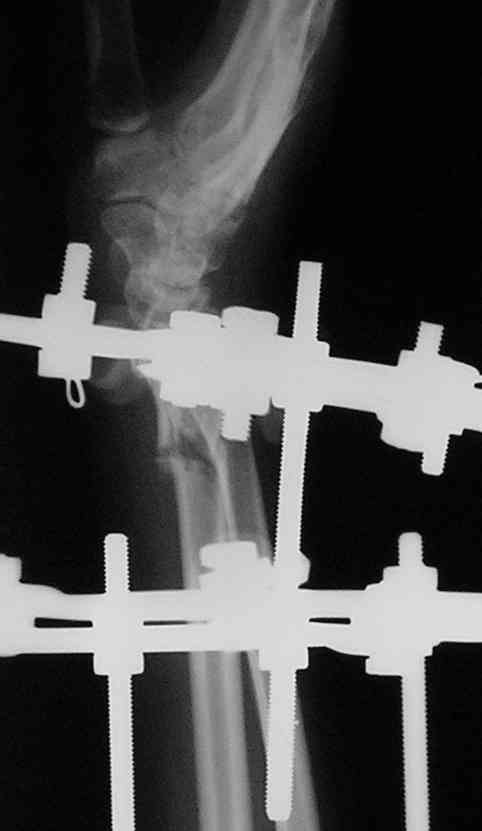

У больного/ой кроме перелома лучевой кости и шиловидного отростка локтевой, разрыв дистального радиоульнарного сочленения, перелом ладьевидной кости и ладьевидно-полулунная диссоциация.

Если позволите свое мнение, не стал бы лечить аппаратом эту травму, перелом луча не консолидировался: открытая репозиция+ костная пластика+ пластина, синтез ладьевидной кости, по возможности шов ладьевидно полулунной связки,

если восстановить связку не представляется возможным, фиксация 2 спицами.

Судя по показанным Рг граммам, очевиден посттравм. артроз лучезапястного сустава, проблема дистального радиоульнарного сочленения(TFCC).

Угол наклона лучевой фасетки в норме в пределах 10-15 градусов, на представленном боковом снимке -может быть чуть больше 15градусов. Выполнив

разгибательную остеотомию луча, ты поставишь фасетку в нейтральное положение и таким образом увеличится угол разгибания , но уменьшится сгибание. По сути, амплитуда движений останется такой же.

Первым этапом я бы убрал пластину с последующей ограниченной резекцией головки локтевой кости(hemiresection and interposition arthroplasty Bowers technique). провести курс реабилитации. если уровень мобильности сустава не

будет устраивать больного, можно рассмотреть проксимальную карпальную резекцию в качестве последующего этапа.